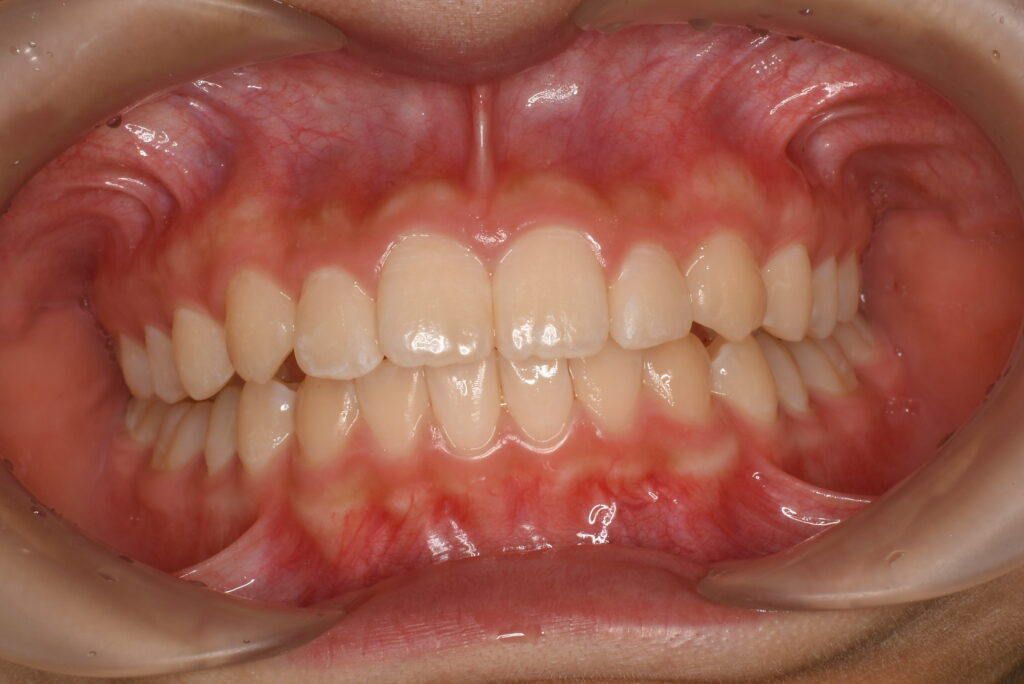

AFTER

歯列全体を整えることで、叢生(歯のガタつき)の改善と咬合のバランス回復を図りました。

必要に応じて、IPR(歯と歯の間をわずかに削る処置)でスペースを確保し、歯の移動をスムーズに進めました。